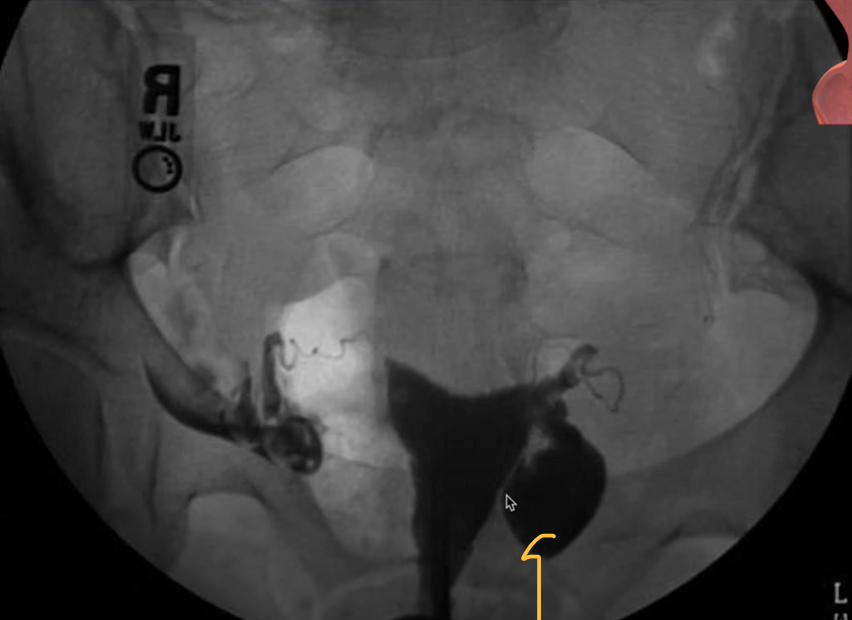

Hysterosalpingogram

Commonly used for investigation of infertility/miscarriage

Assess normal shape of uterine cavity, patency of fallopian ducts, free spill of contrast into interperitoneal space

A hysterosalpingogram (HSG) isan X-ray dye test used to diagnose problems related to fertility.

Hysterosalpinogram

Used to assess patency of fallopian tubes